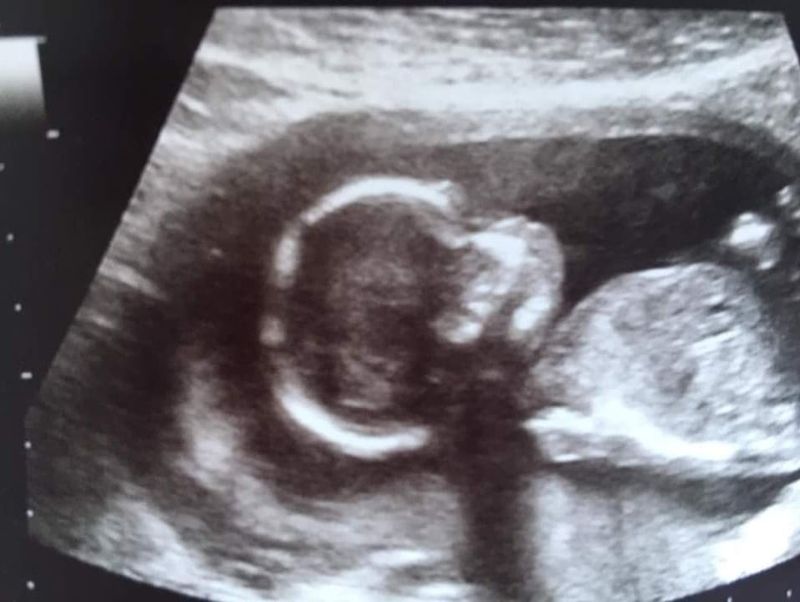

De eerste echo

Ik nam ook contact op met de verloskundige. Omdat op de Clearblue test stond dat ik pas drie weken zwanger was, was het helaas nog te vroeg voor een echo. Ik moest nog minimaal twee weken wachten, voordat ik mijn eerste echo kreeg. Deze had ik uiteindelijk met zeven weken en drie dagen. We zagen toen een kloppend hartje, zo bijzonder.